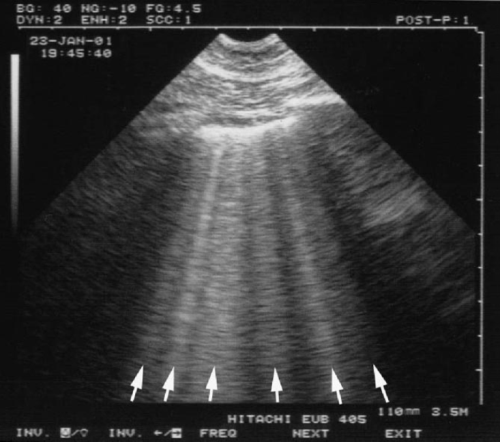

重症肺部超声对呼吸困难患者的鉴别(肺炎,ARDS 心源性肺水肿等)